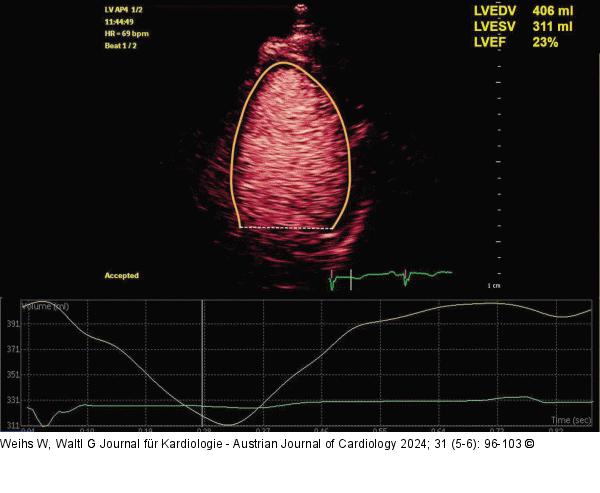

Abbildung 5: Echo Messung der LV-Volumina mittels der Kontrastechokardiographie bei Vorliegen einer dilatativen CM. |

Messung der LV-Volumina mittels der Kontrastechokardiographie bei Vorliegen einer dilatativen CM. |